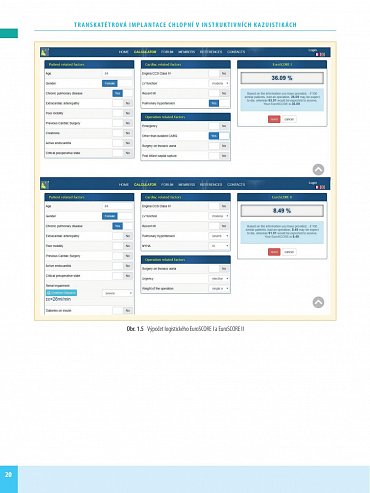

Transkatétrová implantace chlopní (TVI) je minimálně invazivní výkon umožňující náhradu poškozené srdeční chlopně - aortální nebo mitrální. Preferuje se zejména u pacientů s vysokým rizikem komplikací chirurgického výkonu na otevřeném srdci. Kniha obsahuje velký počet pečlivě vybraných kazuistik se stručným schématem diagnostického postupu, diferenciální diagnostikou a technikou operace. Vlastní popis je doplněn množstvím zobrazovacích vyšetření a peroperačních fotografií, které umožní orientaci čtenáře a pochopení základních kroků diagnostiky a léčby.